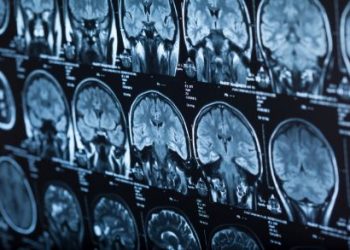

Cancer Near the Ear Can be Treated Successfully – Oren Zarif